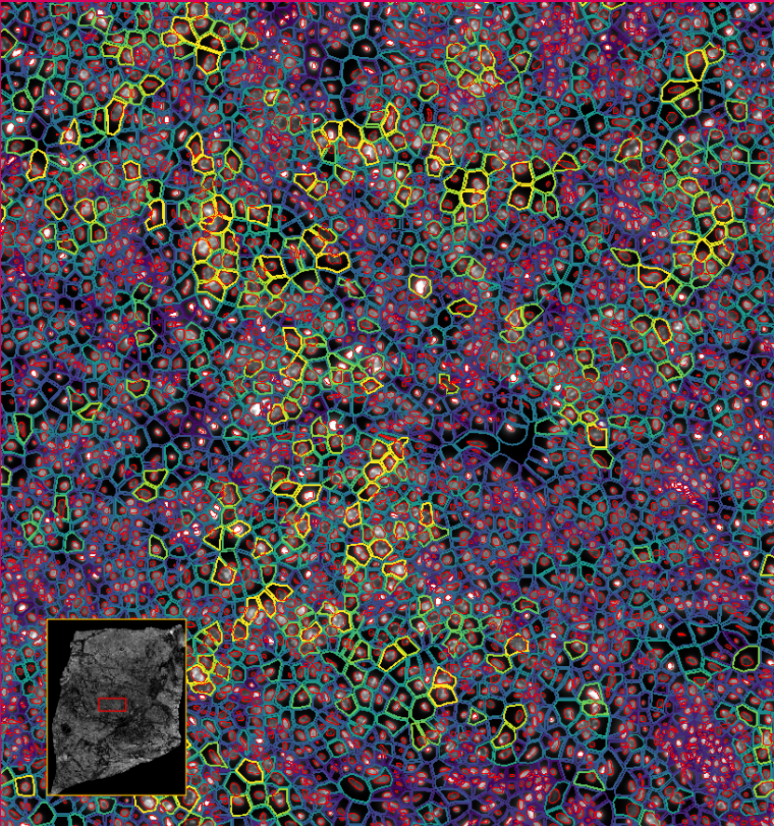

ͼ4-1£ºÊ¹ÓÃDAPI¶Ôϸ°ûºËȾɫ£¬ÍŽáÉî¶ÈѧϰҪÁìÍÆ¶ÏÍêÕûµÄϸ°û½çÏß

ͼ4-2£ºÊ¹ÓÃDAPI¶Ôϸ°ûºËȾɫ£¬ÍŽáÉî¶ÈѧϰҪÁìÍÆ¶ÏÍêÕûµÄϸ°û½çÏß

ͼ5£º½«×ªÂ¼ÌìÖ°Åä¸øÏ¸°û